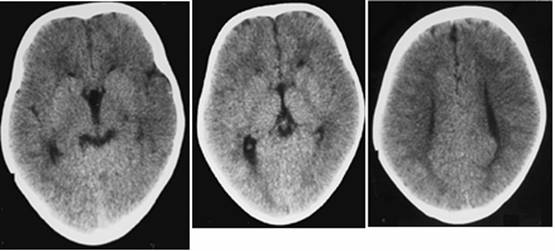

Figure 9

Clinical and image aspects of patient 9

Int J Med Sci Image